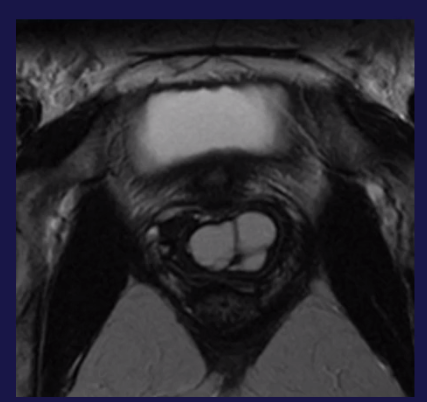

Kyste de Gartner

Paroi antéro-latérale du vagin

Partie haute du vagin

Résidu du canal mésonéphrique